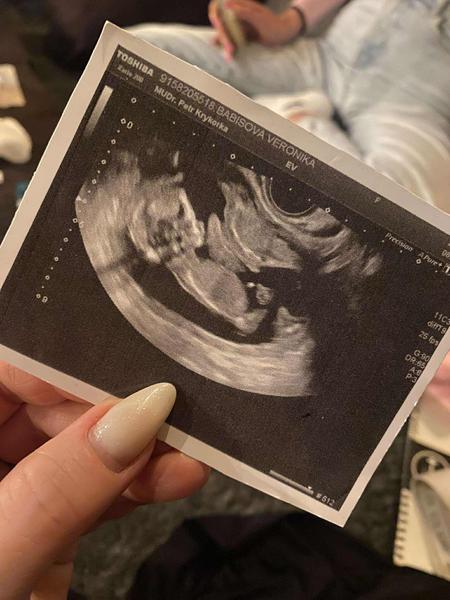

Dokážete odhadnout pohlaví miminka z ultrazvuku?

Ahoj holky, zřejmě dost častá diskuze a otázka. Ale zajímá mě názor “zkušených” rodiček, zda by si dokázaly tipnout na fotce z ultrazvuku pohlaví miminka i u mě? Jde mi jen o tipy, já pohlaví vědět nechtěla a teď jsem tak zvědavá, že se asi pana doktora při příští kontrole zeptám :D

@zuzliseek nakonec čekáme na překvápko k porodu, to bude v dubnu 😀 ale jsem z toho nervózní. Myslíme si, že je tam holčička (naše pocity), ale těžko říct 😅

@angelchild děkuji moc, dr říkala ze si mysli, ze to bude kluk, tak uvidíme 🩵